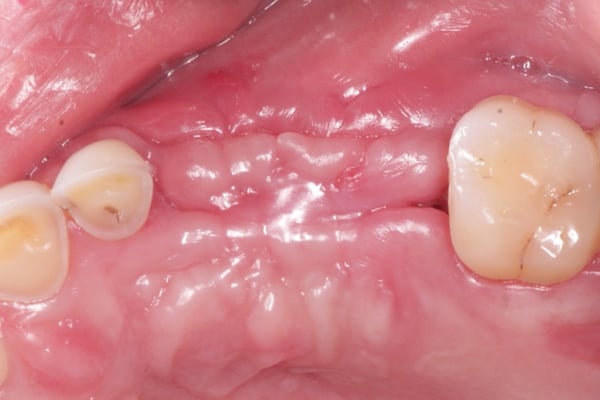

When performing extensive GBR, we want to insure the primary closure of the flap margins over the graft and membrane. In this example, following the placement of the DALI Bone graft and OsseoSeal membrane, the buccal flap was released from the periosteum for passive mobilization (Pictures 1,2,3,4). Prior to suturing the flap margins together at the crest, a periosteal-relief suture is placed in order to prevent any tension from pulling back the flaps (Picture 5). This allows the flaps to stay relaxed without needing to be pulled together. Afterwards, sutures are used to approximate the buccal and palatal flap margins to achieve primary closure that will endure throughout the initial healing period (Picture 6). We see that following 2 weeks of healing, proper primary closure allowed the grafted site to remain covered (Picture 7).